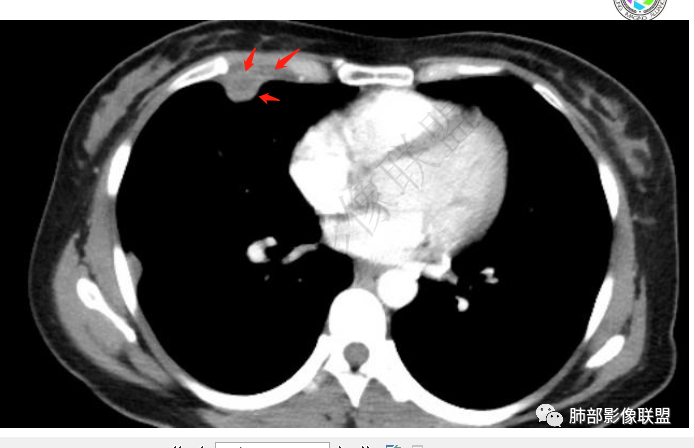

青年女性,胸痛1年,慢性病程

肺内多发小斑片状高密度影,密度不均匀,边缘稍平直

胸膜多个结节,附近胸壁脂肪间隙密度增高,提示有胸壁蔓延或侵犯。

胸膜区病灶周围肺内有小斑片状影,内有条索影,而非放射状,提示提示病灶累及肺内。周围渗出明显——良性肿瘤排除

1.胸膜多发结节,边缘比较光滑,累及胸壁(胸痛也符合,一年),表现为脂肪间隙密度增高,最大的病灶累及肺内,附近有渗出,但是无放射状表现,增强中央有坏死灶,一月后似有缩小,肋骨完整未见破坏,支持炎性可能大!